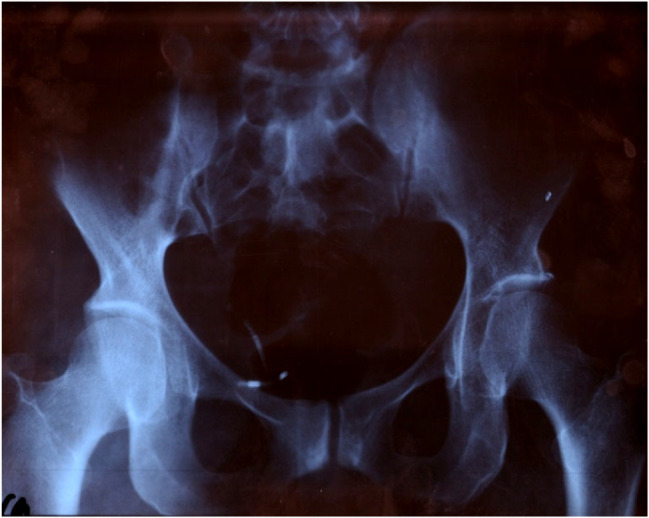

Case presentation: A 35 year-old female 5 gravid, 4 para has been benefited from intrauterine contraceptive device (IUCD) 5 years ago, she was presented to gynecological consultation for chronic pelvic pain with urinary symptoms. There was history of a good IUD insertion 5 years ago, considered expelled after one month of its pose. Physical examination was normal, but a pelvic ultrasound and a plain abdominal radiography allowed the detection of an IUD outside the uterine cavity, but inside bladder. A diagnostic and therapeutic cystoscopy was performed, and the IUD with calculus was successfully removed. There were no postoperative complications.